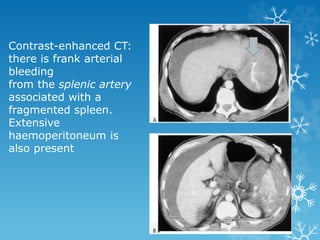

Contrast-enhanced CT:

there is frank arterial

bleeding

from the splenic artery

associated with a

fragmented spleen.

Extensive

haemoperitoneum is

also present